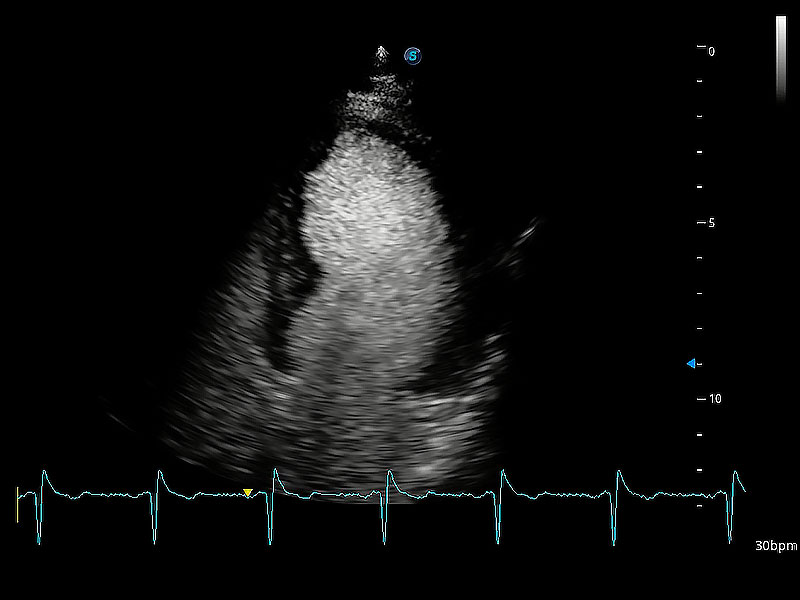

ProPet 80 配備了豐富的心臟探頭群、先進的成像技術(shù)和專業(yè)的心臟測量工具,可幫助動物醫(yī)生為不同體型和生理結(jié)構(gòu)的動物提供心臟和心肌功能的全面評估。

實時用顏色表示心肌組織運動,觀察和定量組織的運動情況,對快速檢測與評估心肌的灌注和活性、電傳導及心肌收縮和舒張功能等均能提供重要的診斷信息。

通過360度任意調(diào)節(jié)3條M型取樣線,在同一心動周期上觀察心臟不同位置的運動曲線,得到準確的心功能測量數(shù)據(jù),有效評估心肌運動及左心室功能。

能夠增加心肌組織與血流之間的區(qū)別。對于心臟掃查困難的動物,可提供更好的心內(nèi)膜邊界的顯示。

能夠基于左心室壁追蹤和辛普森法,自動計算射血分數(shù),支持多個可移動點描跡,與手動測量相比,極大節(jié)省了動物醫(yī)生的時間和精力。